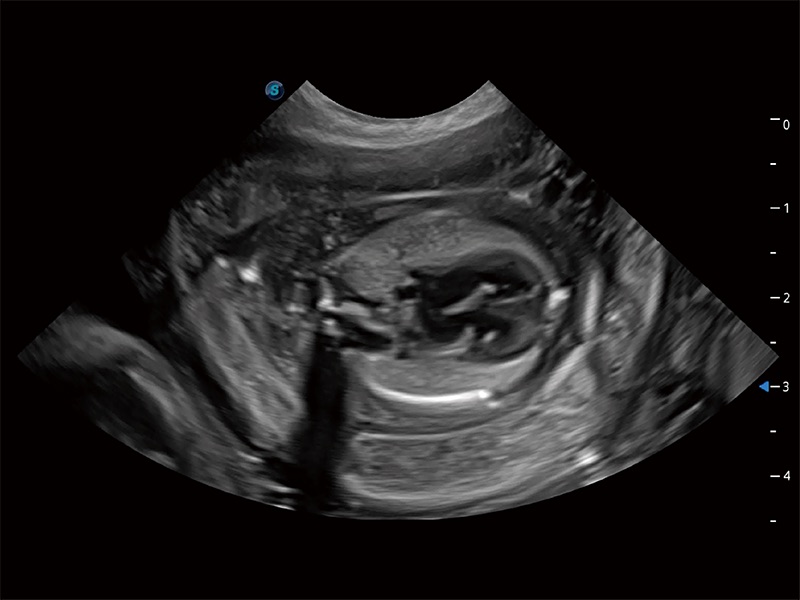

动物是人类最亲密的朋友和最值得信赖的伙伴。milan米兰也一直致力于探索动物专用的超声影像解决方案。全新推出的ProPet系列,是milan米兰在动物超声影像智能化、专业化、精准化的一次跨越式革新。动物不能用言语来表述自己的不适,通过超声影像,ProPet系列搭建了动物医生与不同物种沟通的“桥梁”,为动物医生注入了“治愈之力”。 ProPet 80 是milan米兰匠心打造的一款高端动物专用彩超,采用性能卓越的全新硬件架构,极大提升超声系统的运行效率和数据处理能力,帮助动物医生从容应对日益增多的挑战性病例和日益多样化的临床需求。

高性能和先进的临床应用工具可以为动物医生提供临床信心。ProPet 80 搭载了先进的腹部和浅表应用工具,帮助医生在日常临床实践中发挥前所未有的作用。